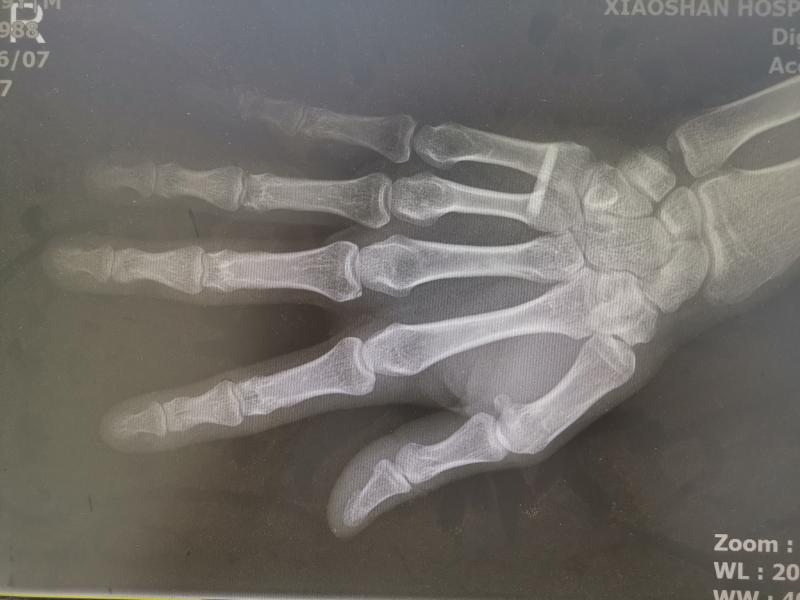

看似简单的动作实际操作起来却并不容易,不仅展示这一技能的餐厅服务员有失手跌落啤酒瓶的情况,不少网友尝试后还表示,“手掌太疼了,而且酒瓶也没有打开。”更有严重的,从网友上传的受伤视频、图片中可以看到,筷子直接扎进手掌中。

熊振飞回忆,三名患者都是吃夜宵发生意外后半夜赶到医院的。“筷子戳进他们的右手手心,有的都从手背穿出了。“有一个人说他手指头发麻,那就相对严重了,是伤到了手部神经。”

熊振飞表示,手掌一般性戳伤需要半年左右的恢复期。